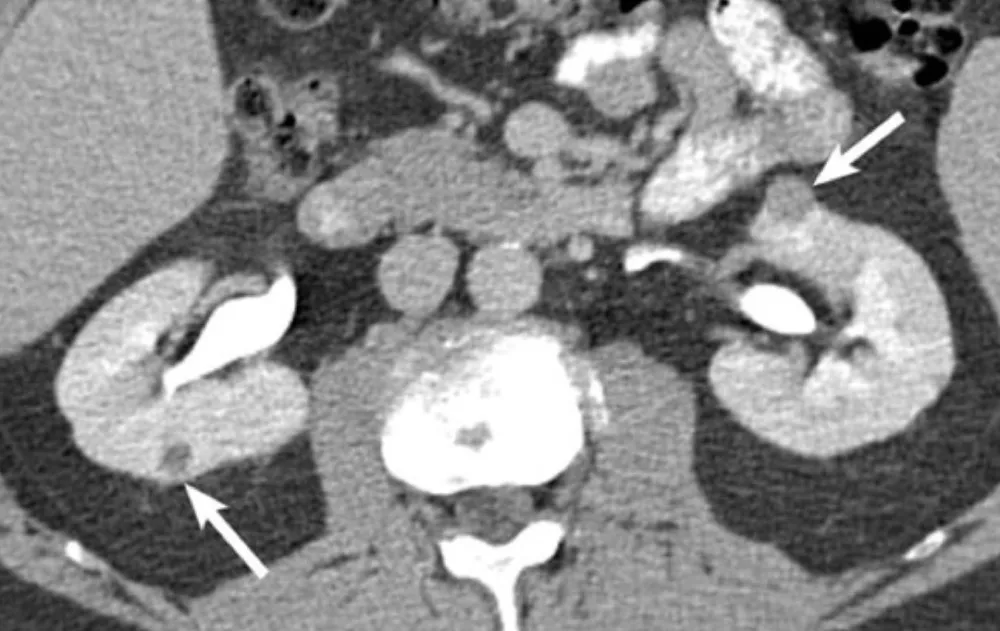

Paciente com antecedentes de carcinoma de células renais claras ressecado previamente, apresenta em exame de controle a seguintes imagens.

Na imagem 1: Um pequeno tumor exofítico com realce se projetando a partir da face anterior do polo superior do rim esquerdo (seta). Além disso, há uma lesão de 4 mm na face posterior do rim direito. Paciente foi submetido à enucleação cirúrgica da lesão renal esquerda. O tumor renal direito foi tratado com ablação por radiofrequência.